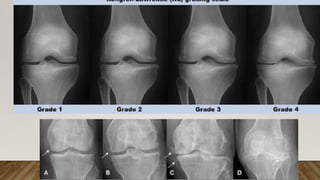

Clasificación de Kellgren y Lawrence

Grados Hallazgos radiológicos

0

(normal)

Radiografía normal

1

(dudoso)

Dudoso estrechamiento de la interlínea

Posible osteofitosis

2

(leve)

Posible estrechamiento de la interlínea

Osteofitosis

3 moderado Estrechamiento de la interlínea

Moderada osteofitosis

Esclerosis leve

Posible deformidad de los extremos óseos

4

(severo)

Marcado estrechamiento de la interlínea

Abundante osteofitosis

Esclerosis severa

Deformidad de los extremos óseos

Clasificación de Kellgreny Lawrence Grados Hallazgos radiológicos 0 (normal) Radiografía normal 1 (dudoso) Dudoso estrechamiento de la interlínea Posible osteofitosis 2 (leve) Posible estrechamiento de la interlínea Osteofitosis 3 moderado Estrechamiento de la interlínea Moderada osteofitosis Esclerosis leve Posible deformidad de los extremos óseos 4 (severo) Marcado estrechamiento de la interlínea Abundante osteofitosis Esclerosis severa Deformidad de los extremos óseos